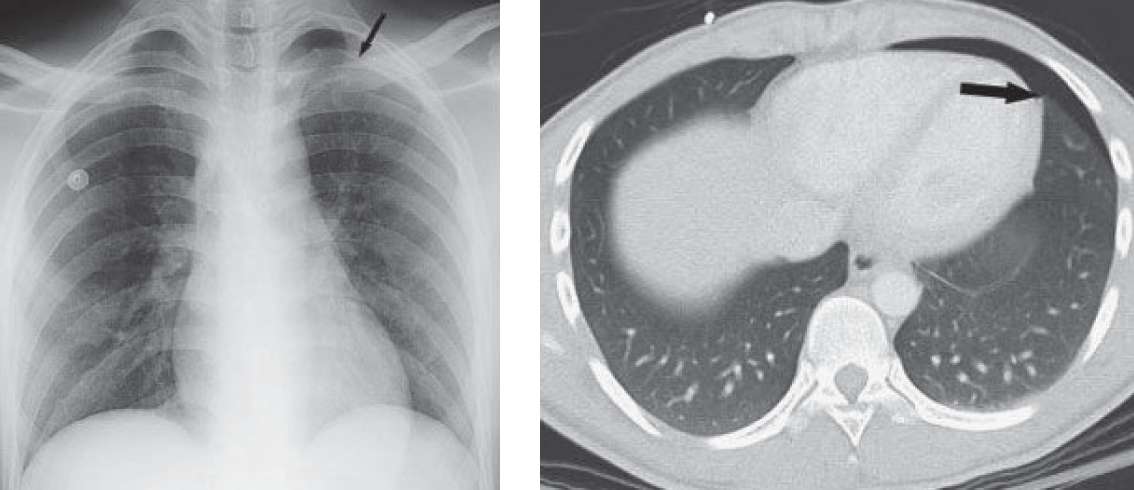

- Follow-up abdominal CT (performed because of the history of trauma) and upright radiograph confirm the small pneumothorax (black arrows).

Follow-up abdominal CT (performed because of the history of trauma) and upright radiograph confirm the small pneumothorax (black arrows).